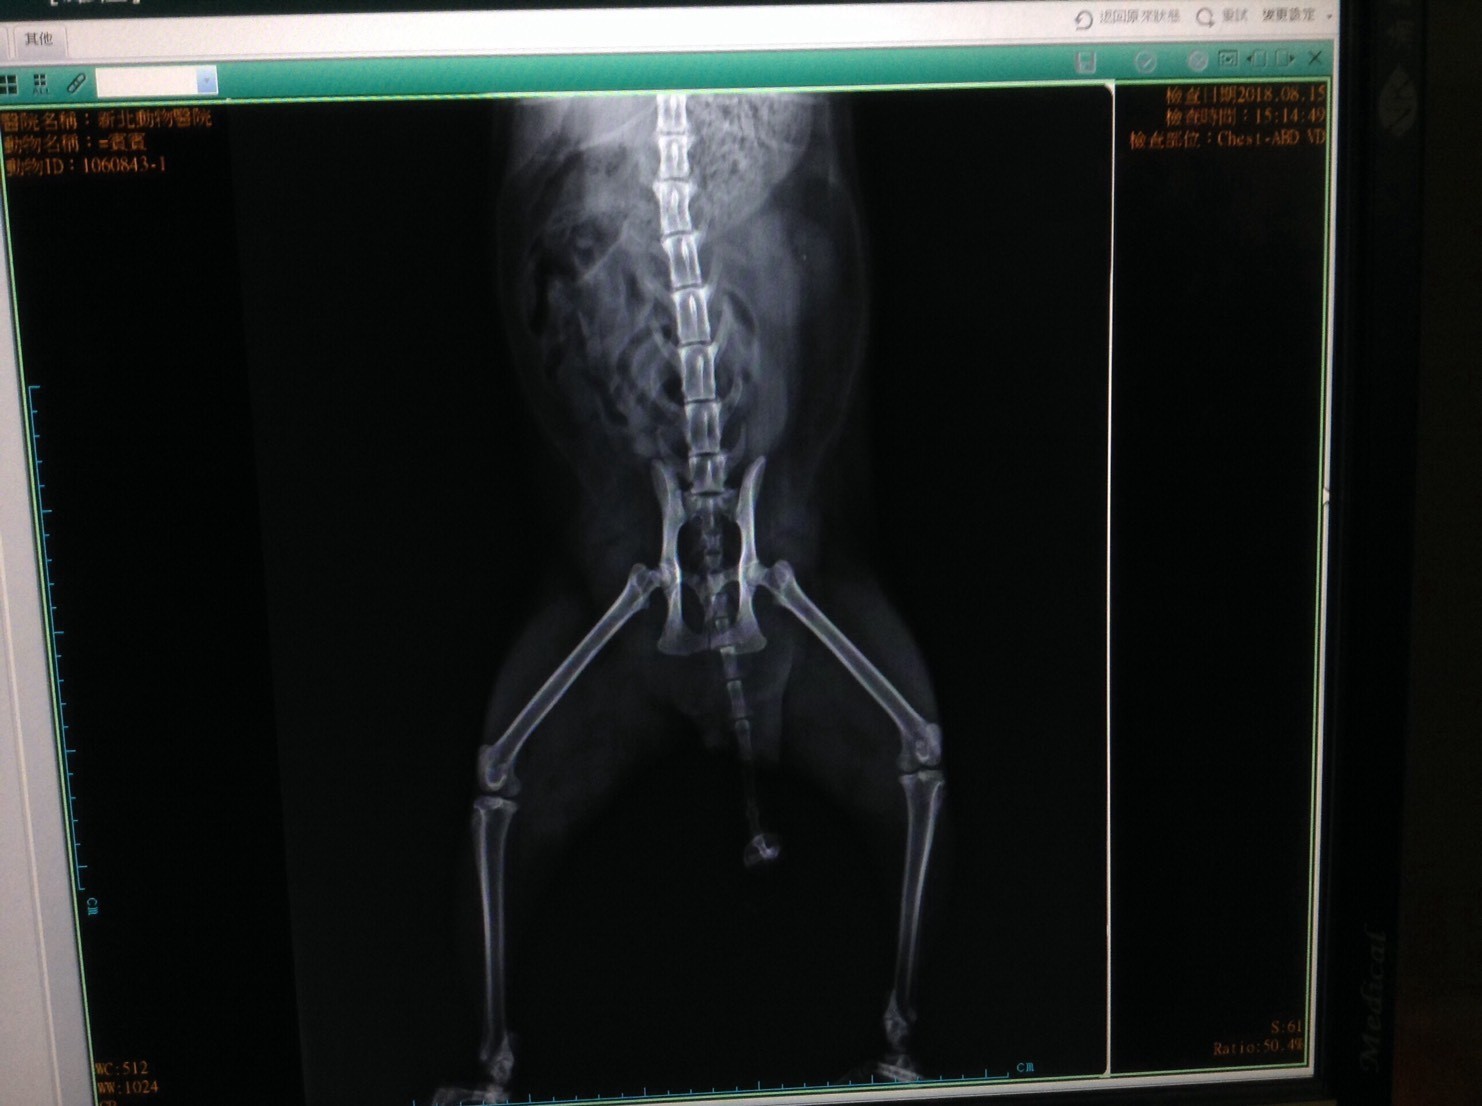

主題: 脊椎受傷的黑白賓士貓 申請者姓名: 施慧君 花色: 申請日期: 2018-10-08 15:49:02 申請者部落格: 申請者臉書網址: 所在縣市/合作醫院: 台北市/內湖維康動物醫院 治療費用: 39300元 需求人數: 83人 已結案 (2024-06-01 13:07:30) 報名人員: Masako(已付款)、ivy x4(已付款)、May x4(已付款)、hank(已付款)、雲荻(已付款)、lunyi x2(已付款)、ying(已付款)、愛瑞爾(已付款)、Patrick x10(已付款)、Ingham Kao、Ingham Kao(已付款)、mint(已付款)、小橘子、小橘子(已付款)、aieda1970(已付款)、JU x10(已付款)、TEST、Daniel Tsai x2(已付款)、Yu-Ling Chang x10(已付款)、王員外的爹(已付款)、波蘿(已付款)、陳彥婷、栗栗(已付款)、ChrisLin x2(已付款)、小胖白(已付款)、Jasmine Lin(已付款)、柚子襪(已付款)、徐雅嬪(已付款)、Cherrie(已付款)、肥咪(已付款)、Peace(已付款)、香菇(已付款)、Pei(已付款)、Angel Lin(已付款)、Naommi x2(已付款)、珮涵、Peko x2(已付款)、Tiffany x2(已付款)、YUN(已付款)、黃琦珊(已付款)、Lulu x2(已付款)、Asaka(已付款)、王可樂 x2(已付款)、李長泰(已付款)、梁莉莉(已付款)、梁莉莉、Kay(已付款)、凱倫(已付款)、 候補人員: 動物病情說明: 2018/8/15 中午救援的一隻街貓賓賓下半身不能移動,送去汐止的新北動物醫院照X光片後,初步判斷脊椎受傷,林院長建議需轉院治療。

2018/8/16 轉院至內湖的維康動物醫院,初步評估可能需要手術來固定脊椎,但是仍需要做斷層掃描來協助病情的判斷。

2018/8/18 維康院長看了斷層掃描的片子,認為賓賓的神經應該不需要脊椎手術,決定讓賓賓穿固定貓咪身體的背板約兩個月,讓貓咪以住院復建的方式來自行恢復神經功能。

2018/9/13 維康又幫賓賓拍了一次X光,換新的背板,X光片顯示賓賓很幸運的是脊椎骨頭中段受傷,沒有傷到椎間盤,所以目前走路及大小便都正常,預估再兩個禮拜之後應該可以接回居家照護。